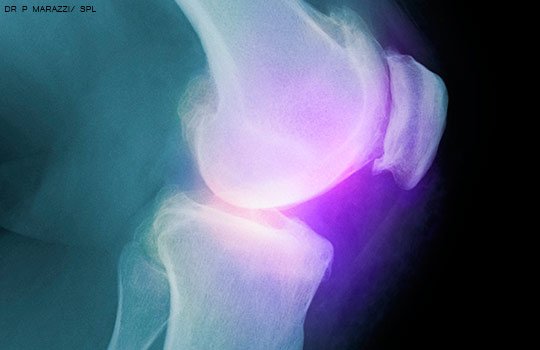

Efecto de la cirugía temprana versus terapia física sobre la función de la rodilla en pacientes con desgarros de menisco no obstructivos. Ensayo clínico aleatorizado ESCAPE

JAMA, 2 de octubre de 2018Los resultados muestran la no inferioridad de la terapia física en comparación con la cirugía temprana con meniscectomía parcial artroscópica para mejorar la función de la rodilla autoinformada en pacientes con desgarros meniscales no obstructivos.

Recomiendan no hacer artroscopía en artrosis de rodilla

Una guía de práctica clínica desaconseja la cirugía artroscópica para la artritis degenerativa de la rodilla y los desgarros meniscales. BMJ, 10 de mayo de 2017